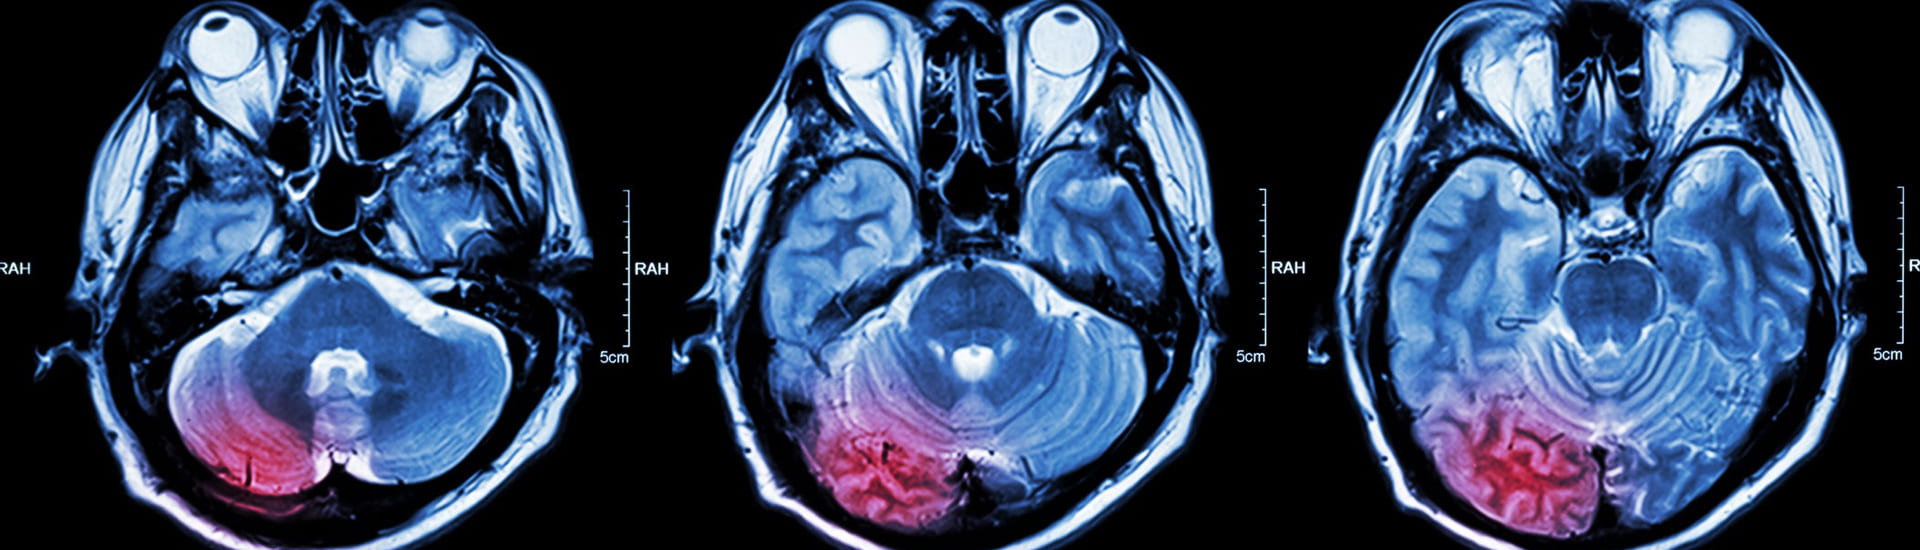

• Cerebellar tremor, caused by damage to a part of the brain called the cerebellum or the pathways that connect to it. Patient with multiple sclerosis, brainstem trauma, and stroke may experience this type of tremor.